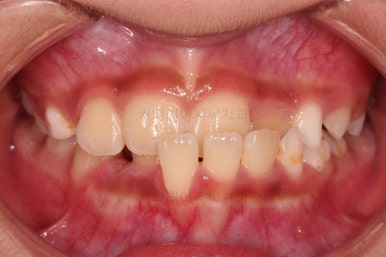

1. 초진

초진 시 입안의 모습입니다.

가장 눈에 띄는 건, 아랫니가 윗니보다 앞에 나와있는 부정교합인데요.